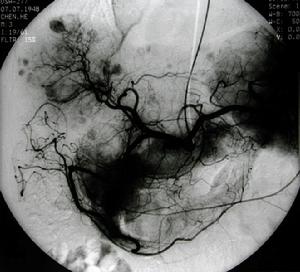

肝臟類癌通常缺乏特殊的症狀體徵組織學上與肝細胞癌相似,且臨床上又特別罕見因此診斷較為困難。肝臟類癌的定位診斷常常有賴於B型超聲顯像選擇性肝動脈造影、電子計算機X線斷層掃描(CT)或肝放射性核素掃描,甚至磁共振顯像(MRI)檢查

2.肝動脈栓塞化療(TACE) 肝動脈栓塞化療是20世紀80年代發展的一種非手術的腫瘤治療方法,近年來套用於肝臟類癌的治療也取得了較滿意的效果,是非手術療法中的首選方案多採用碘化油混合化療藥物栓塞腫瘤遠端的血供,再用明膠海綿栓塞近端肝動脈使之難以建立側支循環,致使腫瘤組織缺血壞死化療藥物常用CDDP 80~100mg、絲裂黴素(MMC)16~20mg阿黴素(ADM)40~60mg5-氟尿嘧啶(5-FU)1000mg,肝動脈栓塞化療應每隔4~6周進行一次反覆多次效果更好。